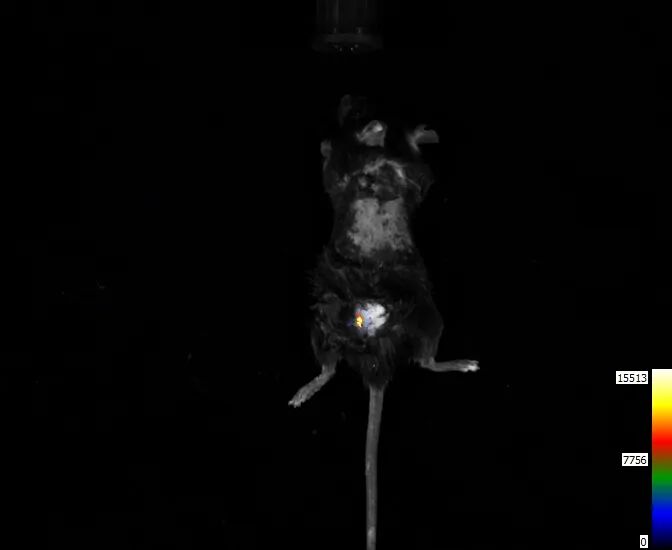

肿瘤研究:如脑胶质瘤、肺癌等方面

①1*107个荧光素酶标记的脑胶质肿瘤细胞,颅内原位注射,随后腹腔注射底物荧光素,用IVScope8500拍摄

(使用CLINX IVScope 8500拍摄)

②1*106个荧光素酶标记的脑胶质肿瘤细胞,颅内原位注射。2*106和1*107个荧光素酶标记的脑胶质肿瘤细胞于背部左侧皮下注射,随后腹腔注射底物荧光素